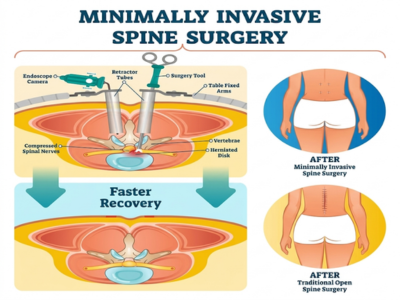

Spine Disorders

Care for conditions like herniated discs, sciatica, and spinal stenosis using advanced medical and surgical options.

Minimally Invasive Techniques

Procedures designed to reduce pain, shorten hospital stay, and support faster recovery.